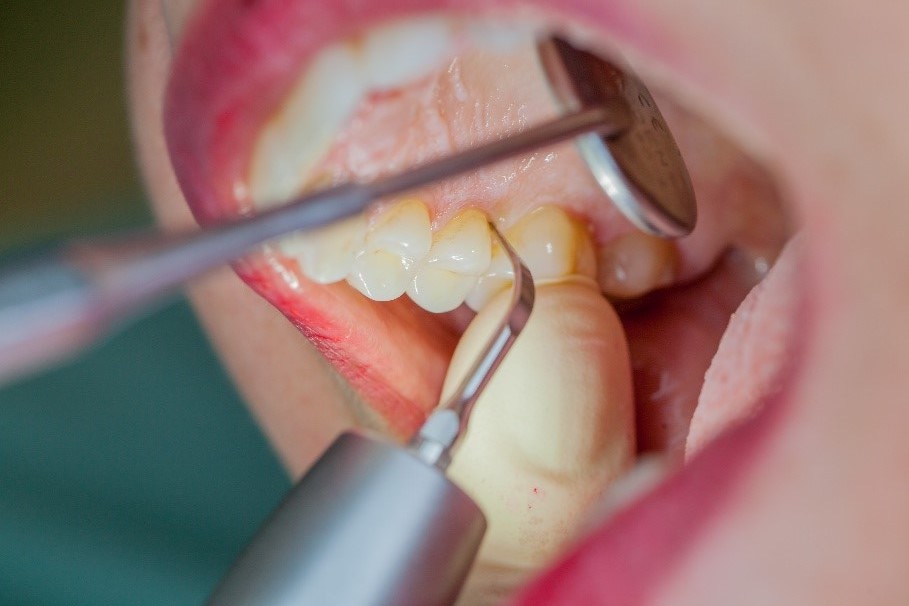

Removal of subgingival coatings (debridement) is carried out using sonic or ultrasonic devices and special periodontal tips as initial periodontal treatment (Fig. 3). Manual instruments can also be used. Further surgical and/or regenerative measures may be necessary, depending on the situation.